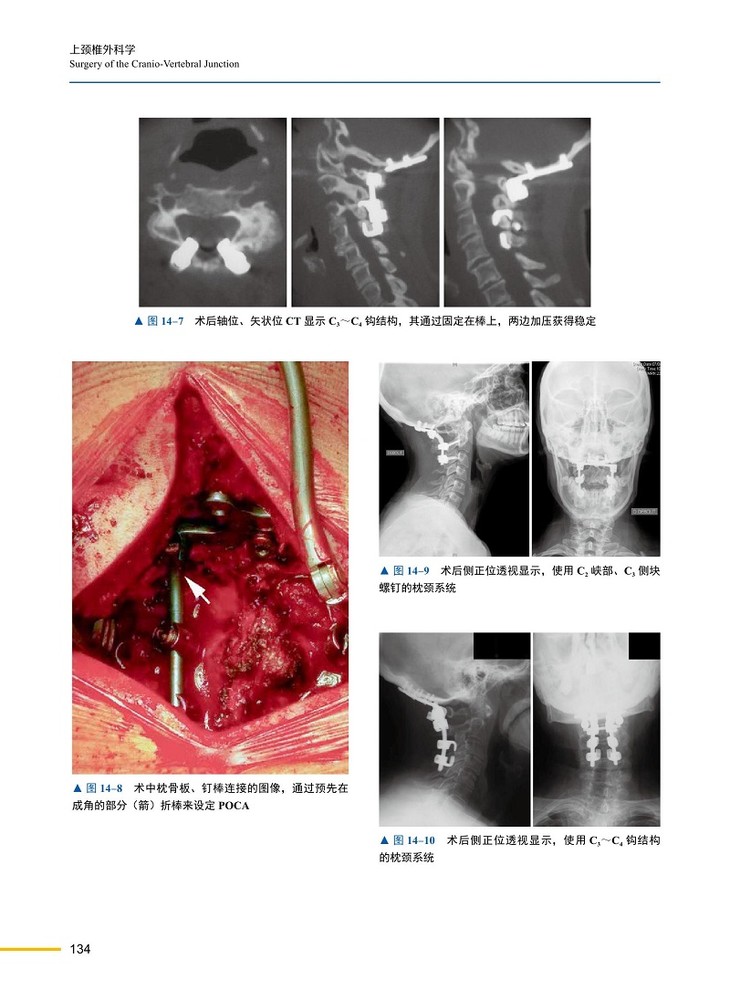

本书第一篇主要阐述了颅颈交界区的解剖、影像学、生物力学和矢状位平衡;第二篇则侧重于围术期的处理和导航、增强现实等辅助技术的应用及临床价值;第三篇主要介绍了寰枢椎手术技术、技巧,不仅包括传统的手术入路、内固定技术,还包括微创技术和介入技术等新技术、新进展;第四篇则重点介绍了上颈椎疾病的治疗,几乎涵盖从常见的创伤、肿瘤、畸形到罕见的上颈椎疾病的所有治疗。

本书引进自Springer出版社,由国际上享有盛名的脊柱外科专家联袂编写,是一部全面介绍常见及罕见上颈椎区域疾病的临床著作。全书共四篇35章,概要介绍了人体解剖学特点,强调了生物力学及矢状位平衡的概念,阐述了围术期的重要注意事项及术前和术中影像学技术的应用,描述了累及颅颈交界区的各种疾病及治疗。纵览全书,内容系统,图表丰富,理论与实践兼备,既可为从事上颈椎疾病诊疗工作的医师提供指导,也可方便广大骨科医生在临床工作中查阅参考。